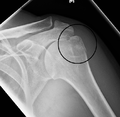

Fracture of the greater tubercle of the humerus

Fracture of the proximal humerus with involvement of the greater tubercle